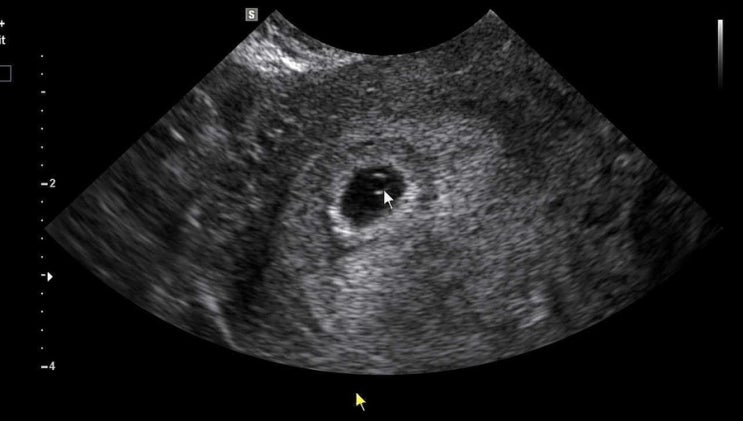

기다리고 기다리던 심장소리 들으러 가는 날 콩알만한 것이 잘 붙어있을라나 증상이 아무것도 없어서 체감...